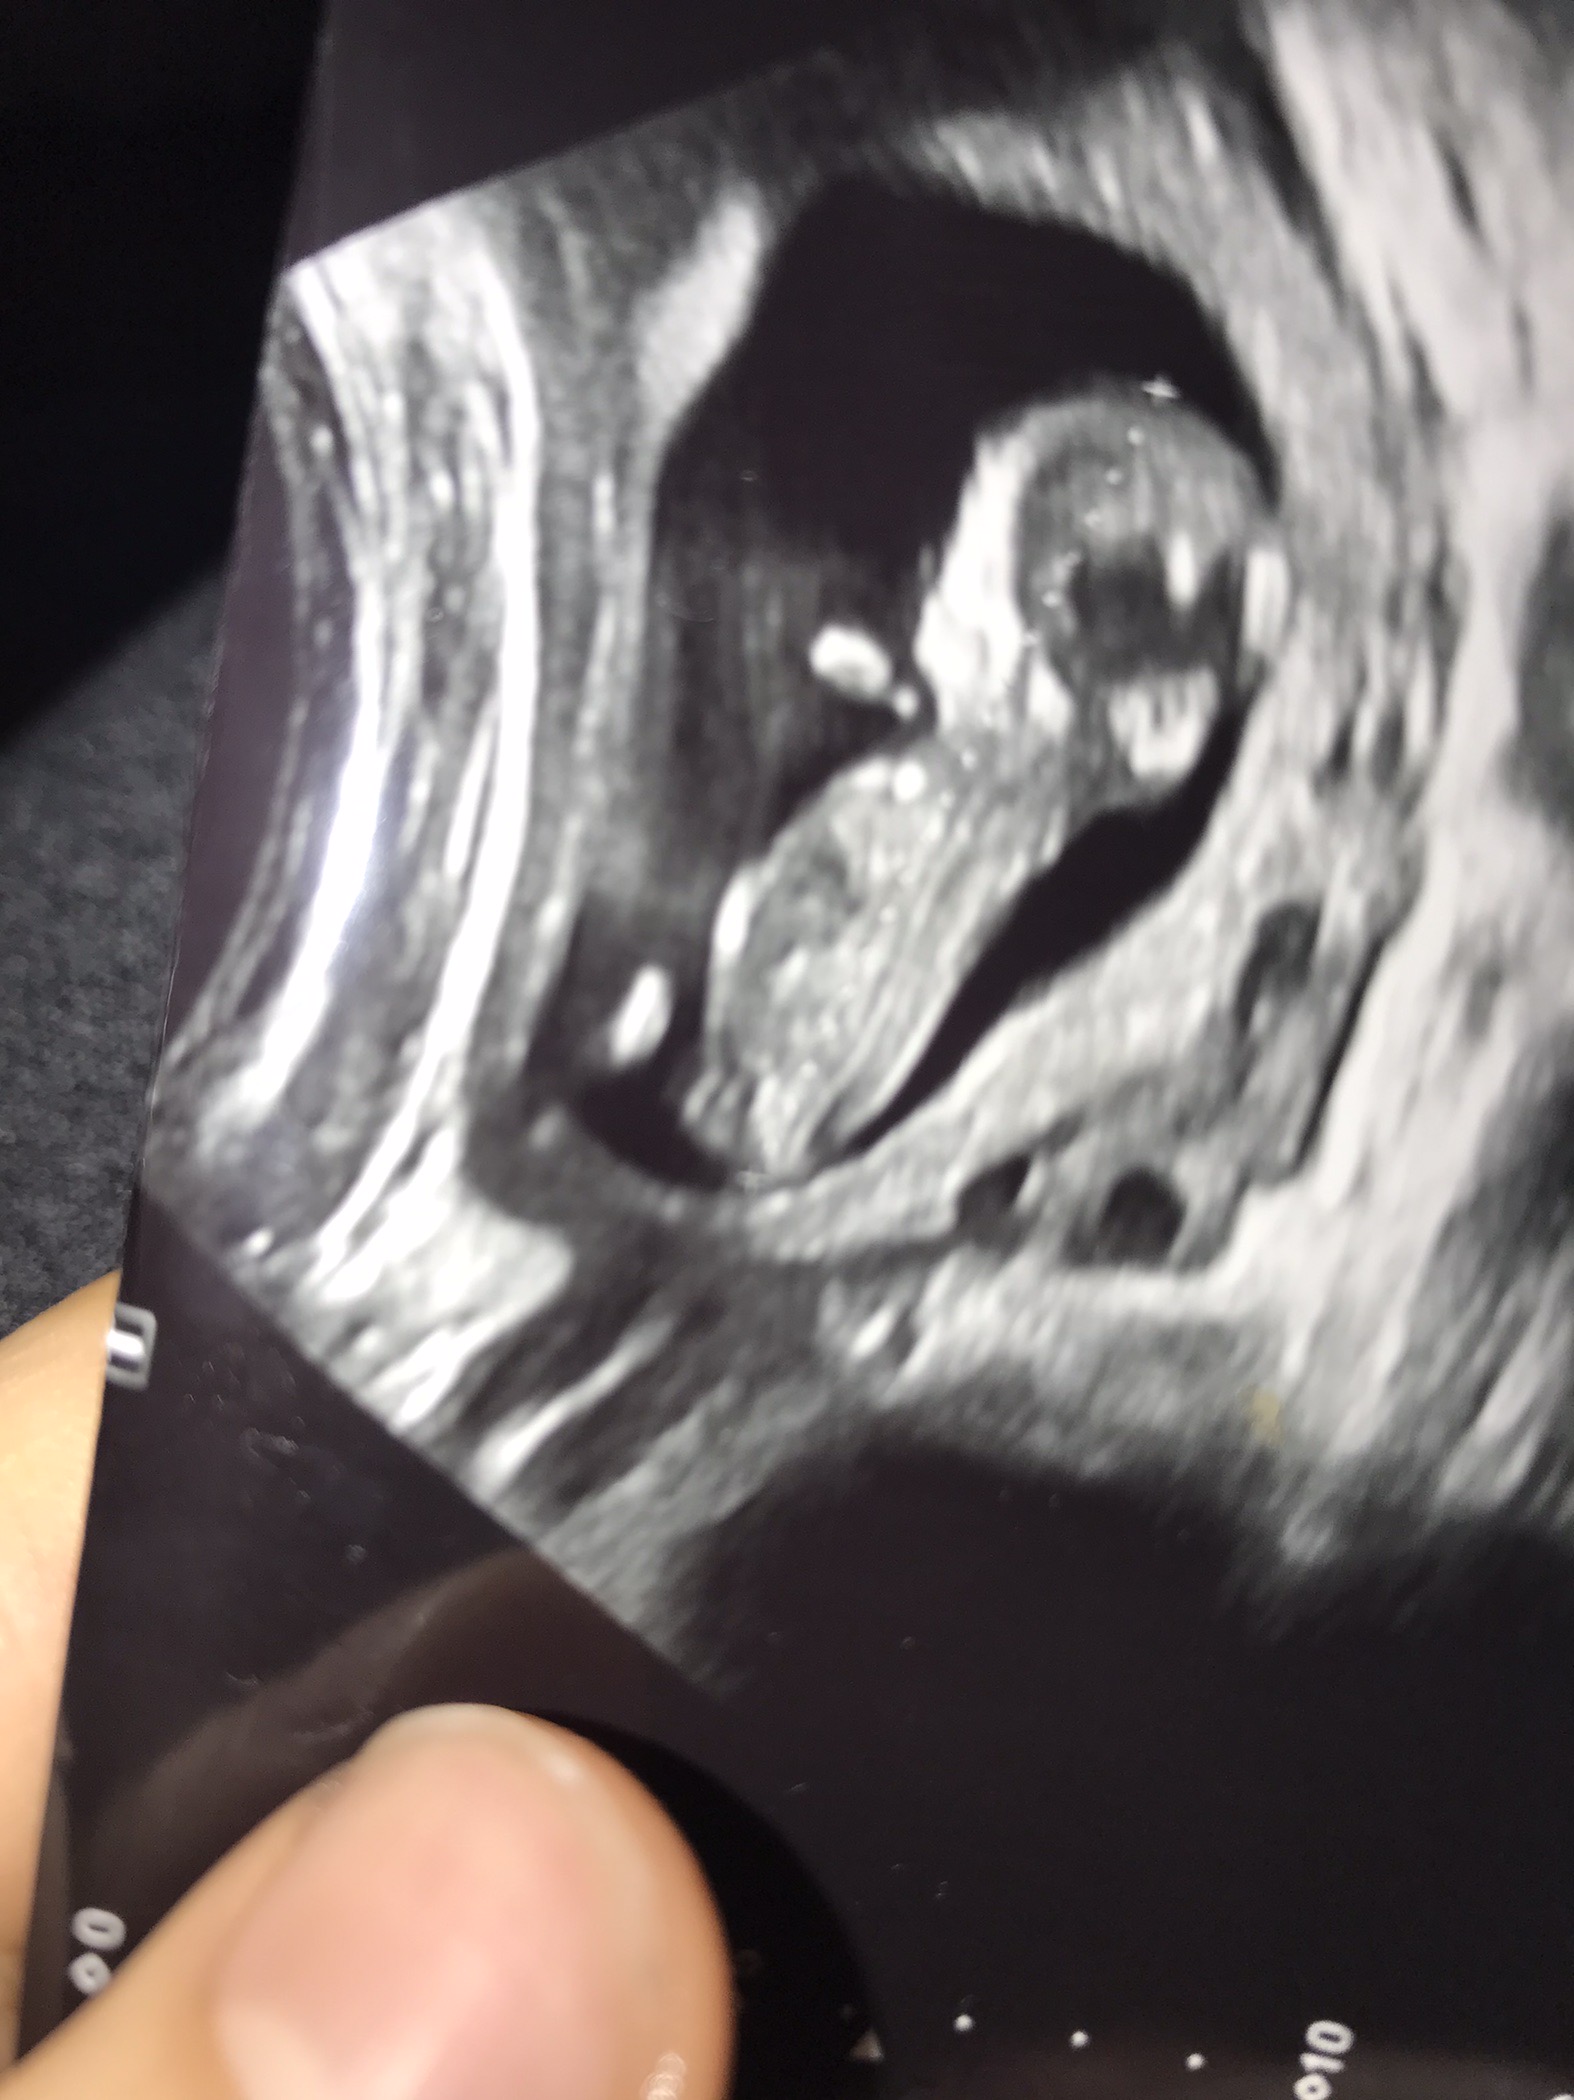

Dediğim gibi şuan ki fotolardan çok çıkıntı görünmüyor kız gibi görünüyor diyebilirim emin olmamakla birlikte sonraki ultrason görüntüsü ile yine bekleriz 🙂:hamis:

Selamlar hayatım gönderdiğin resimleri inceledim ama pek fazla bir şey belli değil bu konunun birinci sayfasında resimlerin nasıl gösterilmesi gerektiğini göstermişiz yani doktordan bu şekilde bir resim istersen net şekilde sana yardımcı olur